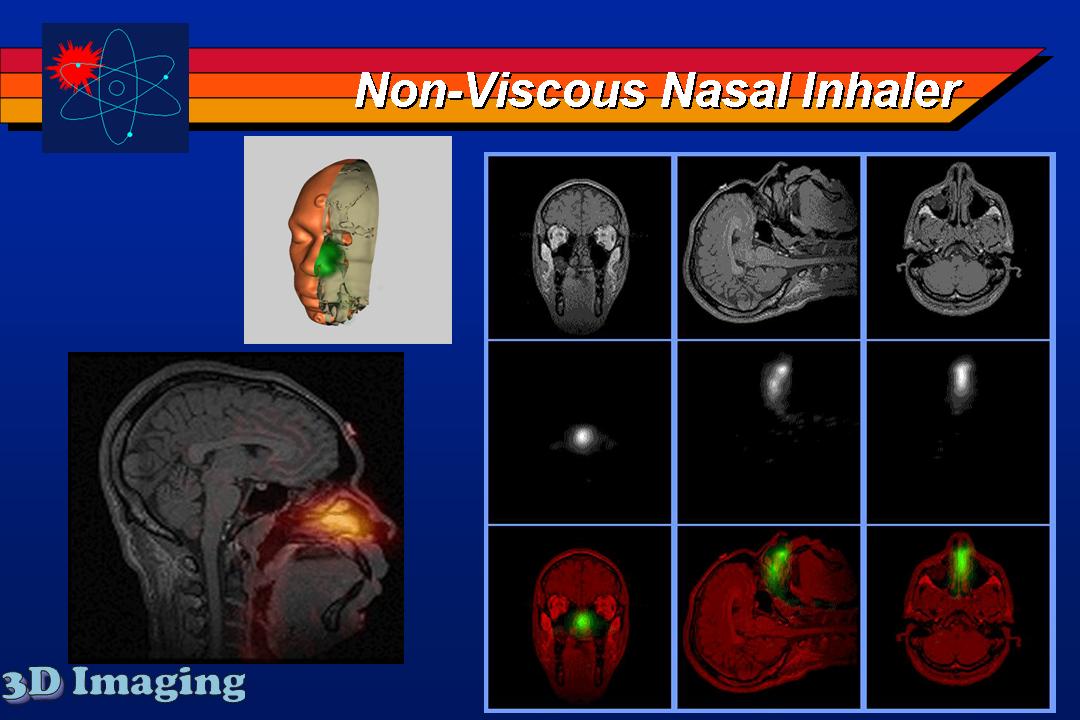

Several inhaled drug formulations were studied by radiolabeling the active ingredient (several different steriods) with C-11 or F-18, formulating that ingredient as the dosage form (different MDI, DPI, and nebulizer formulations), and performing quantitative PET studies of the regional biodistribution and kinetics.

Click on images to see additional examples, larger versions, and videos.